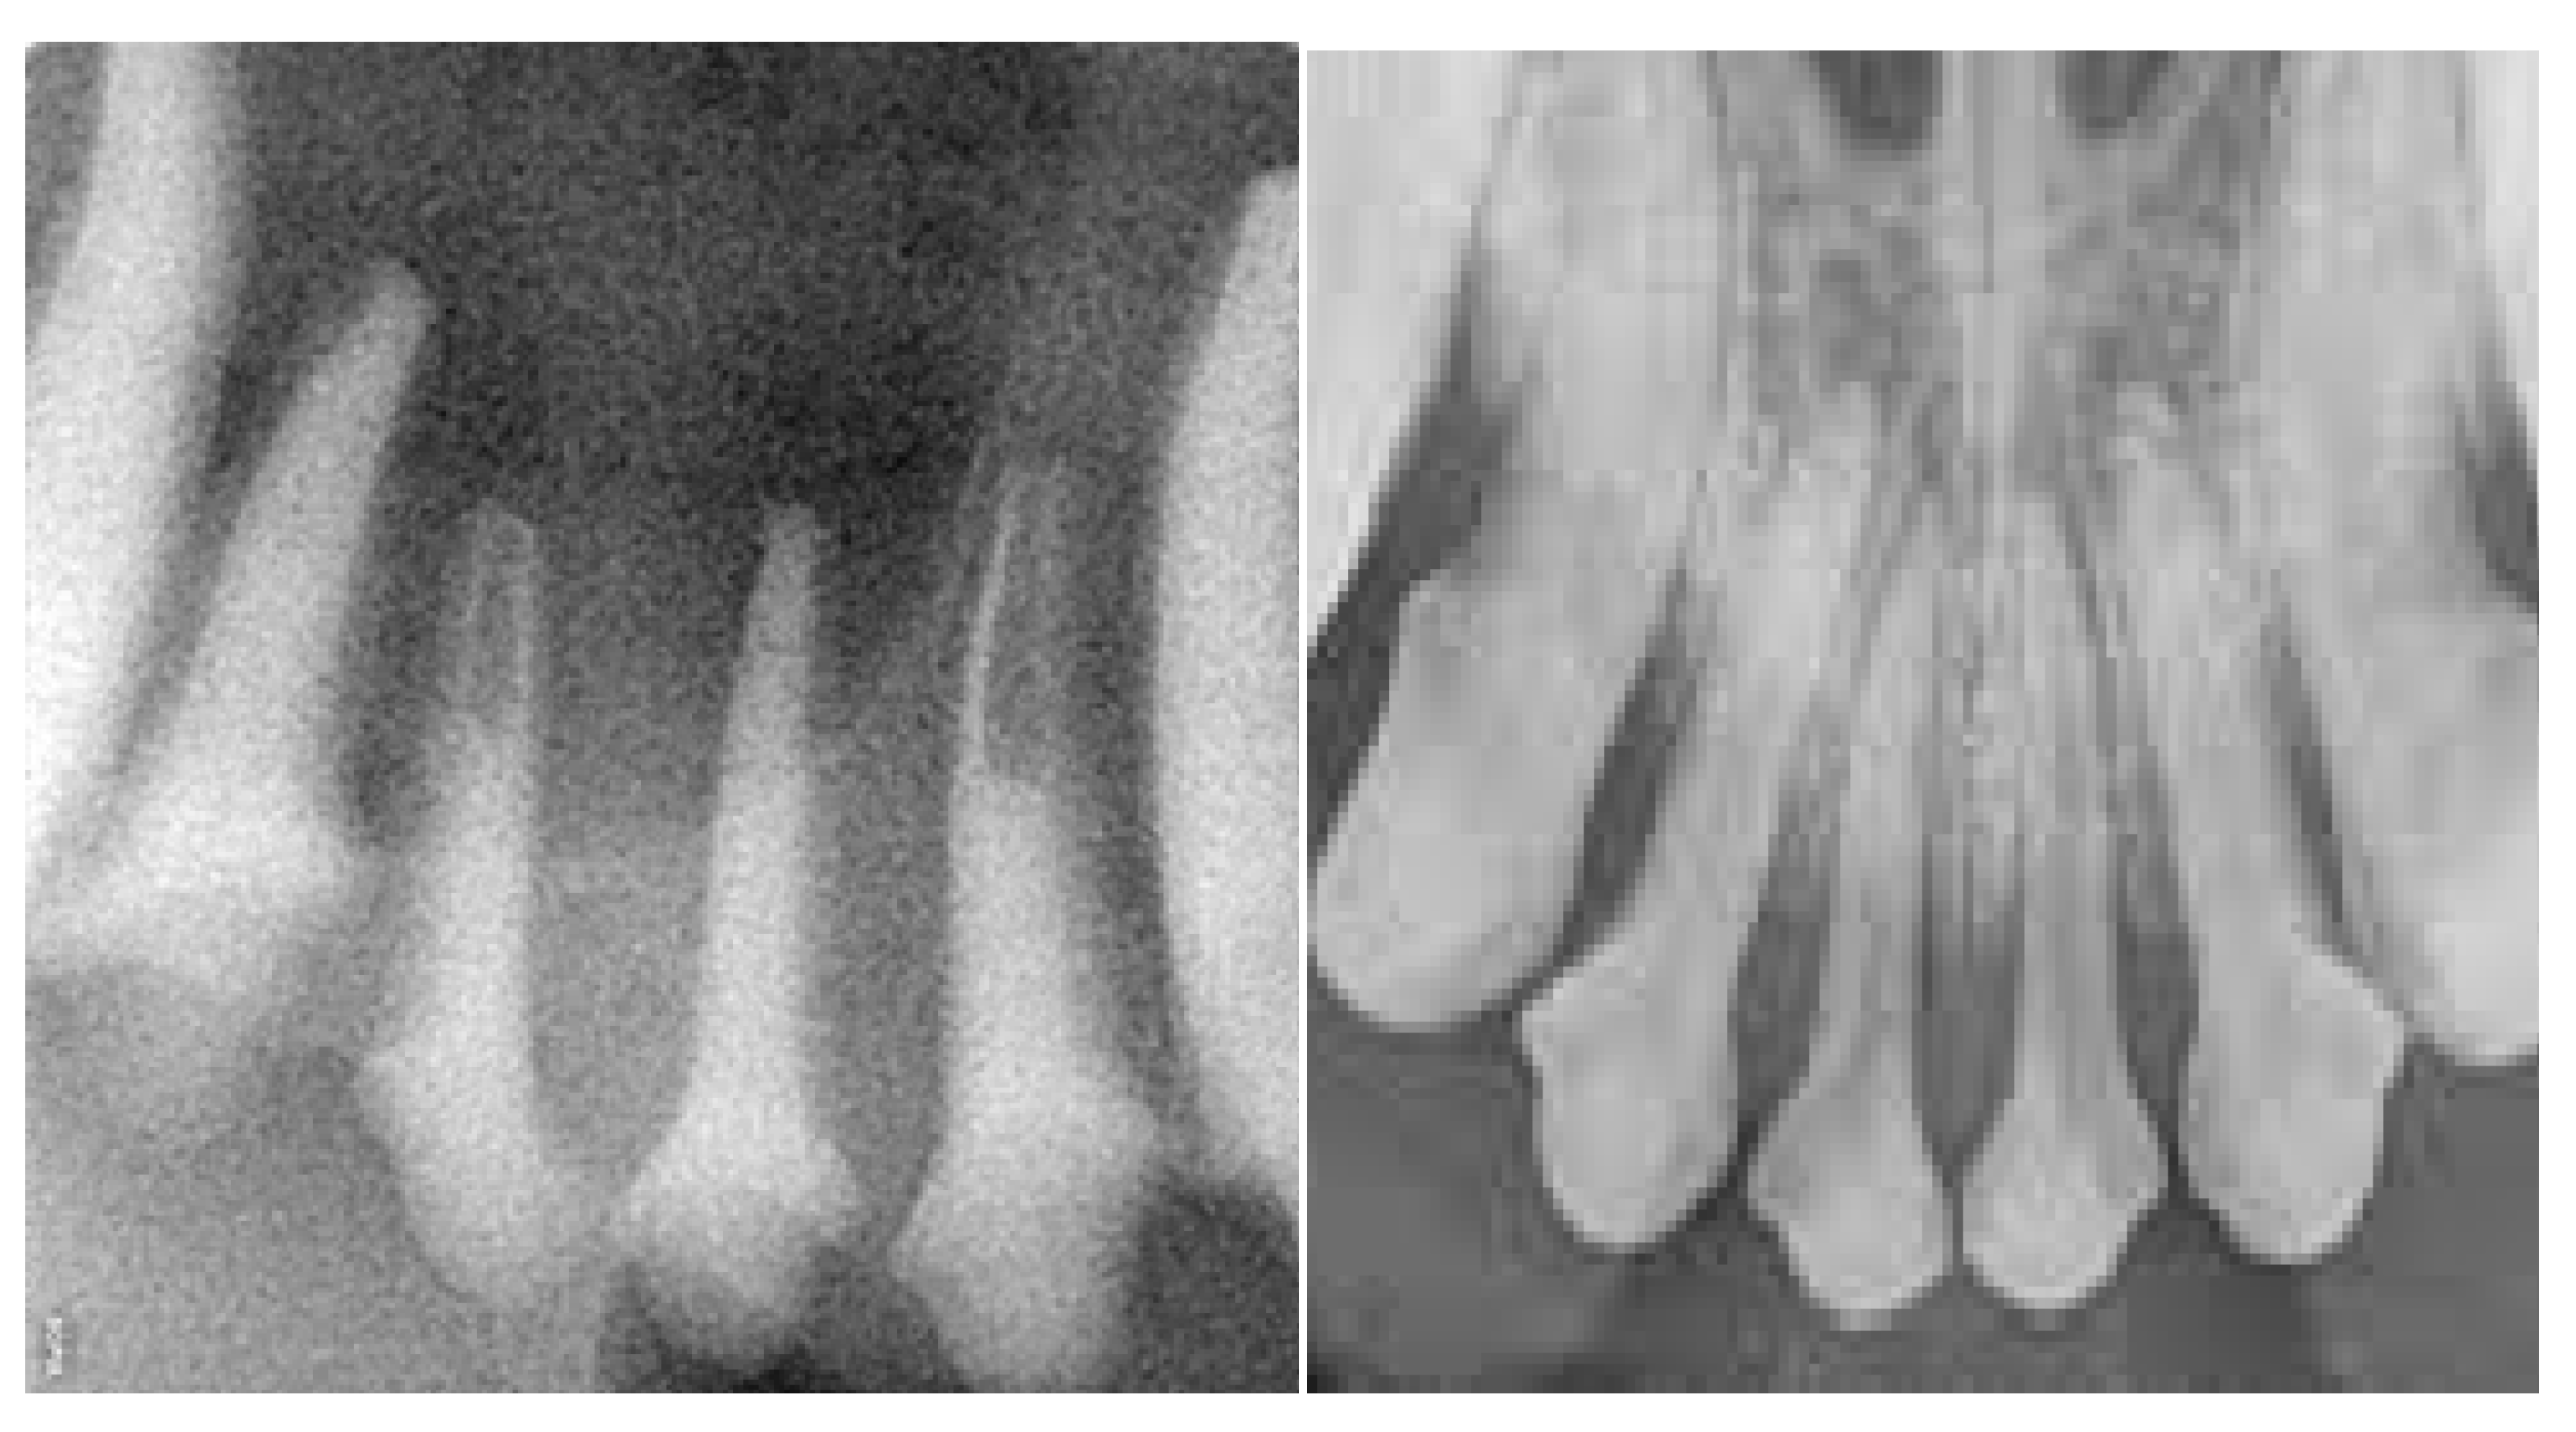

At the time the study was conducted, three sets of jaws were available for use to teach different skillsets. (i) One set was used to teach scaling and polishing that included simulated calculus painted onto the teeth. Once dry, an ultrasonic scaler could be used to remove the simulated calculus as in a live patient. (ii) A second set with radiodense teeth was used to teach radiographic positioning (Figure 3). (iii) A third set was used to teach extractions, which included a simulated periodontal ligament. These techniques were used to perform gingival flap creation, alveolar bone removal, tooth elevation and tooth extraction (Figure 4). Components were colored in a realistic fashion to allow for the identification of different simulated tissues.

This study asked three veterinarians to provide face validation for the models prior to their use in laboratories. We asked two diplomates of AVDC (one of them being the fourth author) and an experienced primary care clinician with an interest in small-animal veterinary dentistry (fifth author) to participate. They identified that the teeth of the radiology models had poor contrast. In response, VSI improved the contrast of the models. A subsequent assessment by the same veterinarians identified that the improved models included a variety of teeth that were found not to be strictly anatomically correct, and that some tooth roots had hollow appearances. However, the models were deemed to be appropriate for use in teaching radiographic positioning. In conclusion, the models were deemed to be appropriate for use to practice cleaning, radiographic positioning, and extraction skills, and were considered especially useful for learning instrument-handling skills and gaining familiarity with oral anatomy.

Figure 3. Radiographs of the Maxillary Incisors of the HFM (left) and a Live Patient (right).

Vetsci 10 00526 g003